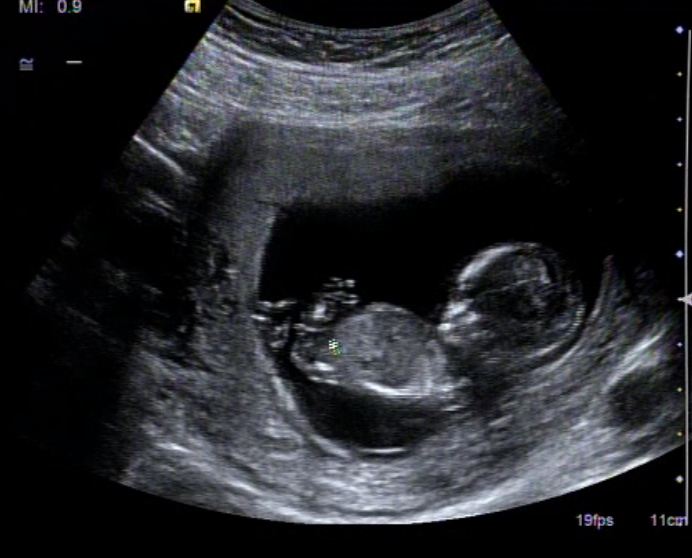

well our elective scan is on Thursday and I'll be 15+2 (last time, baby was measuring 4 days ahead). I am going to add 4 more pics right below and would love to get a few more guesses as what I have so far is a bit controversial. Not sure if the white line in pic 4 is even a nub. As a reminder, the baby measured 13 weeks at the time of this scan. Thanks!

Attachment 9577

Attachment 9578

Attachment 9579

Attachment 9580